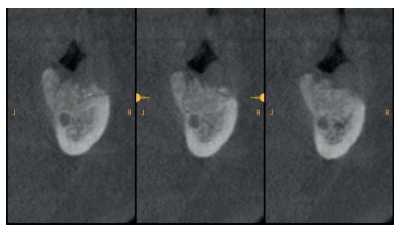

Al quinto mes se realizó un CBCT de control, para evaluar la homogeneidad en la zona y se planificó la colocación de un implante corto de 5 x 6 mm de Proclinic® (Figura 9) al mismo tiempo que fue tomada una biopsia de la zona. Se procedió a inyectar la misma anestesia que en la primera cirugía, se elevó un colgajo a espesor total y se tomó una biopsia con trefina de 3.5 mm de la zona injertada (Figura 10). En la misma zona donde fue realizada la toma de biopsia, sin pasar ninguna otra fresa, se colocó el implante empleándolo como expansor, de modo que se condensasen las paredes que rodeaban al implante (Figura 11).

La muestra tomada se envió a analizar al Servicio Diagnóstico de Patología Oral y Maxilofacial del Dr. Aguirre en Vizcaya. El resultado de la biopsia describe “tejido óseo trabecular vital. Se observan múltiples fragmentos irregulares de dentina tubular, reconociéndose neoformación ósea en íntimo contacto de algunos de ellos”, además de aportar cortes microscópicos (Figura 12). Debido a que se observó una zona con una densidad muy baja, se recomendó la re-entrada a los 6 meses para evaluar la calidad del hueso regenerado con dentina.